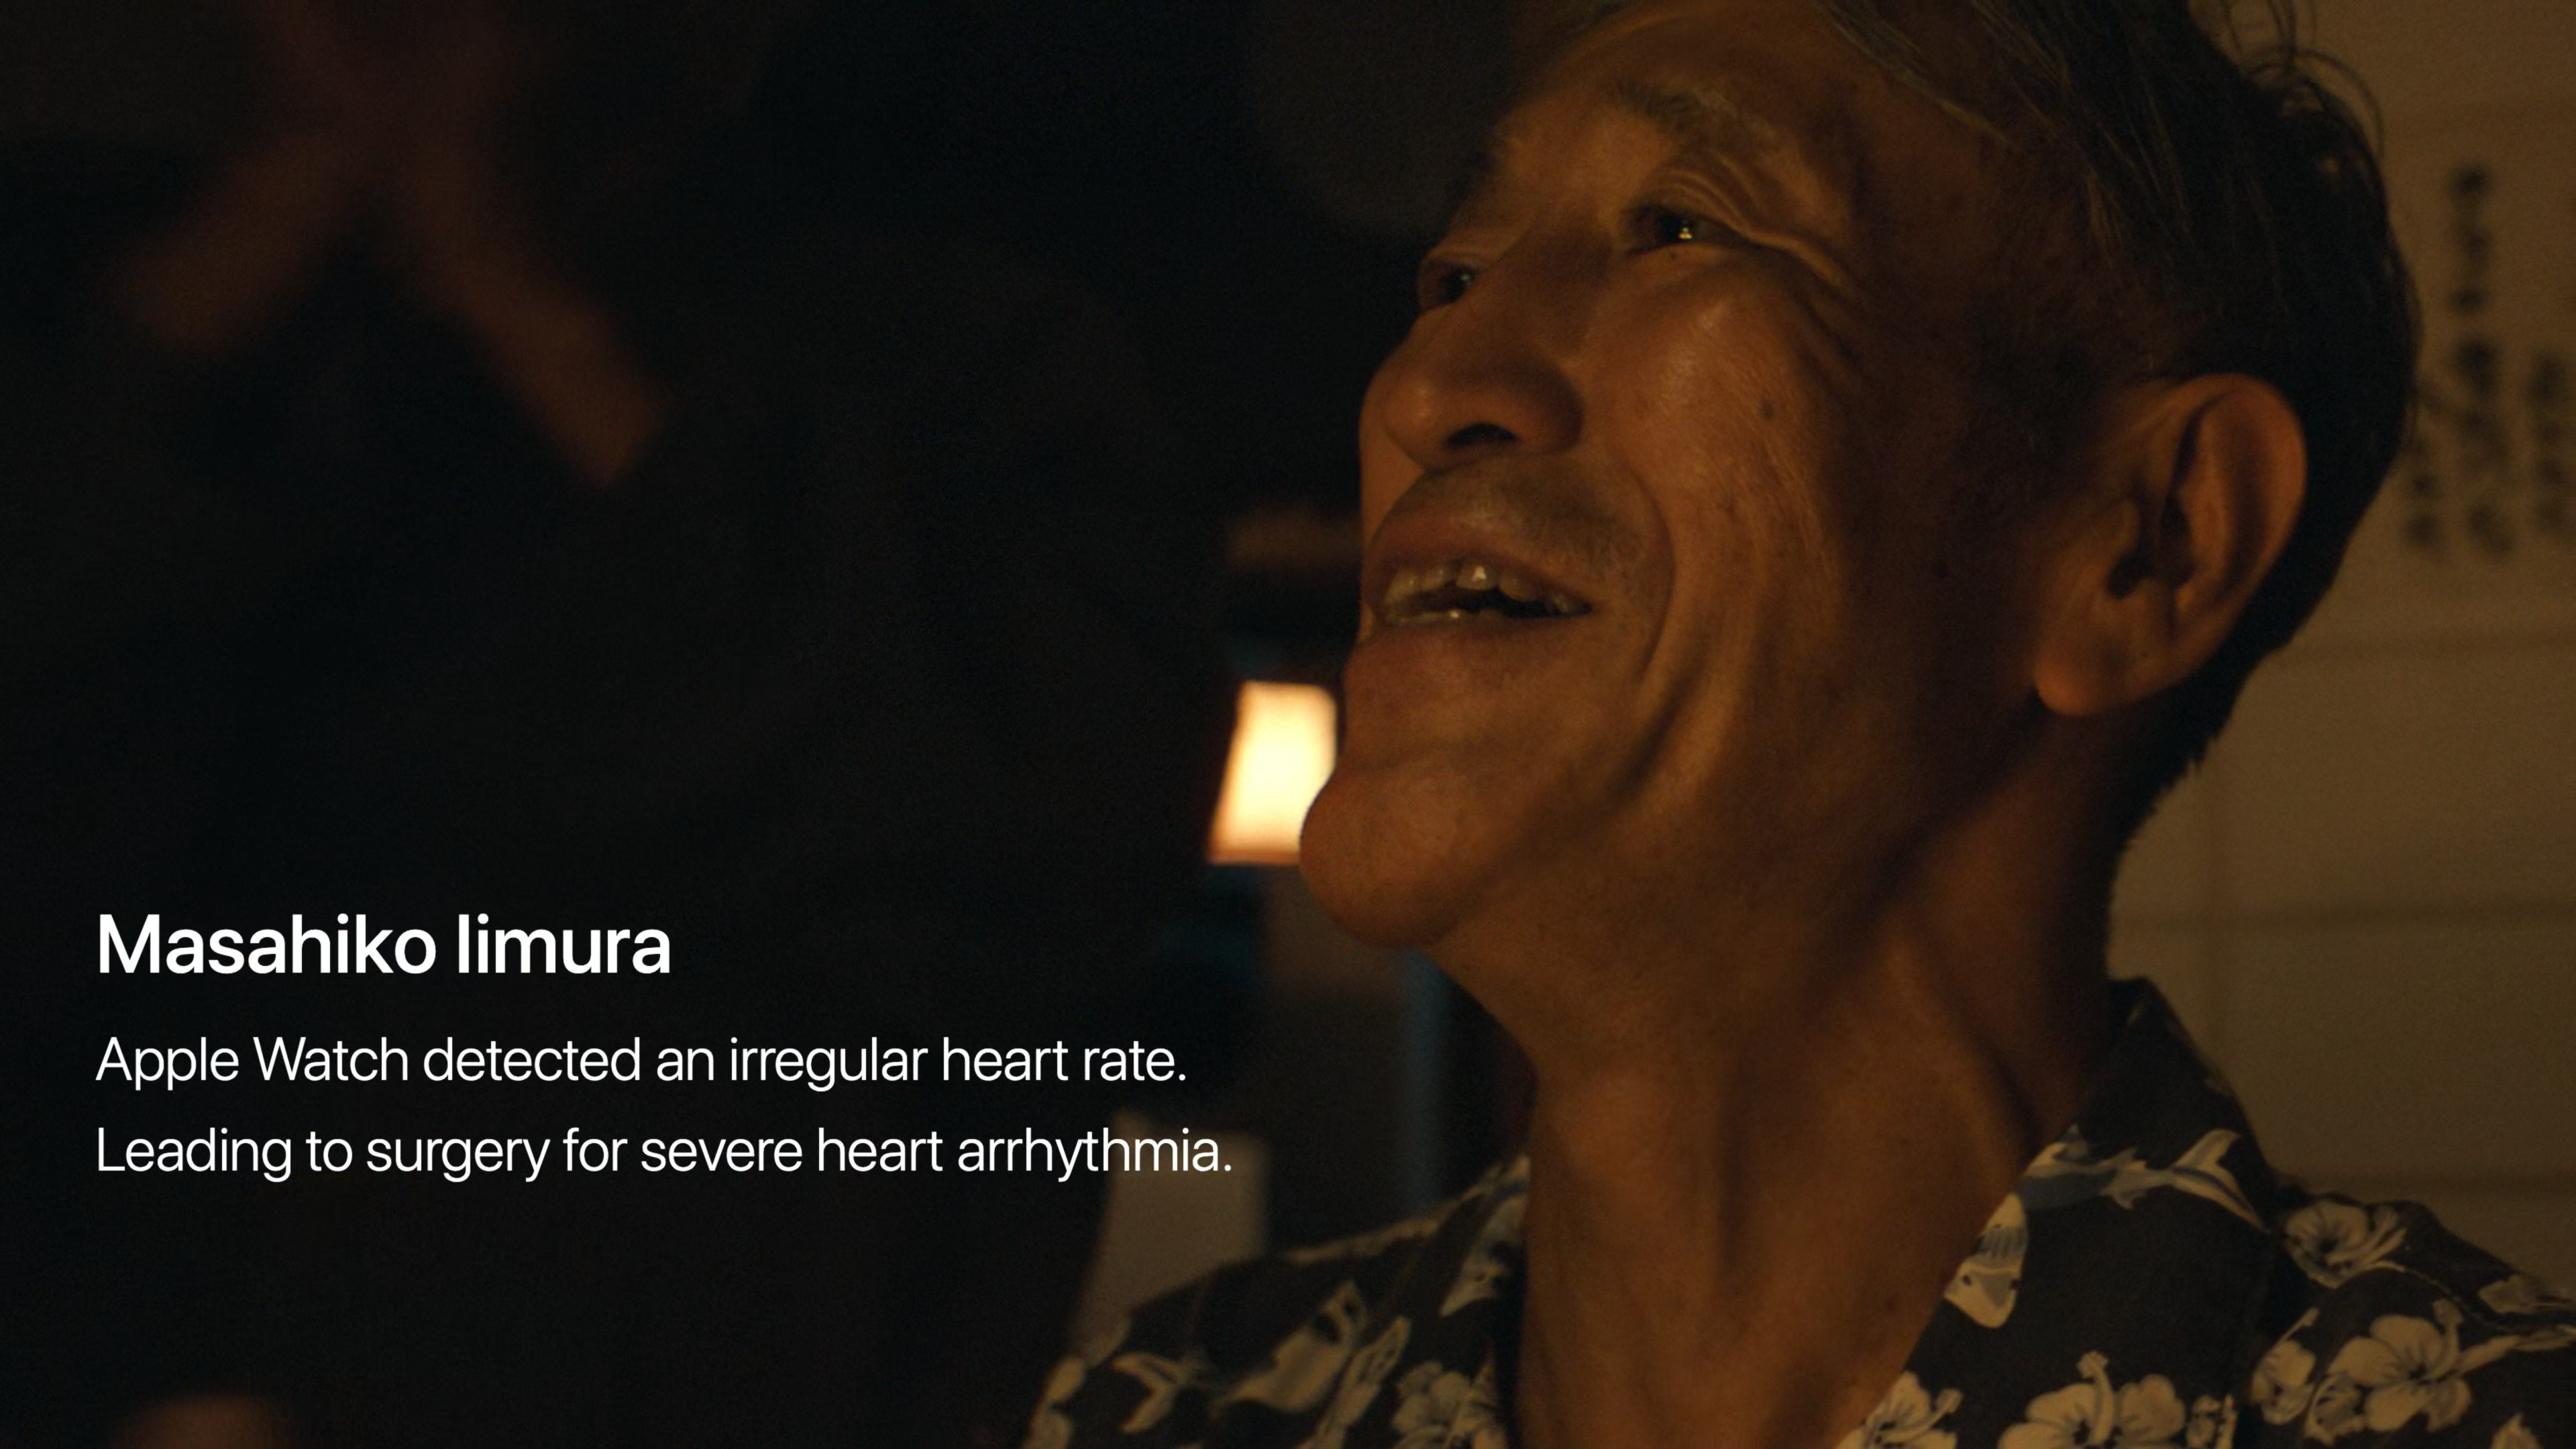

Již několik desítek minut před začátkem se na webu Applu objevilo logo letošní Keynote za doprovodu skladby Natural od Jackie Mendozy a Magic in U od Cub Sport. Jakmile odbila sedmá, animace se změnila v tradiční úvodní video se záběry na různé lidi, jak v průběhu dne od probuzení až do noci používají nejrůznější Apple zařízení. Po přehrání emotivního videa, zmiňujícího mimo jiné přínos Apple Watch a dalších jablečných produktů a jejich funkcí pro lidské zdraví, jsme se mohli pokochat klasickým přeletem nad Apple Parkem. V němž nás již přivítal Tim Cook a zahájil nejdůležitější Apple Keynote letošního roku, na které se představí iPhone 15, iPhone 15 Pro (Max), Apple Watch Series 9 a spousta dalších novinek.